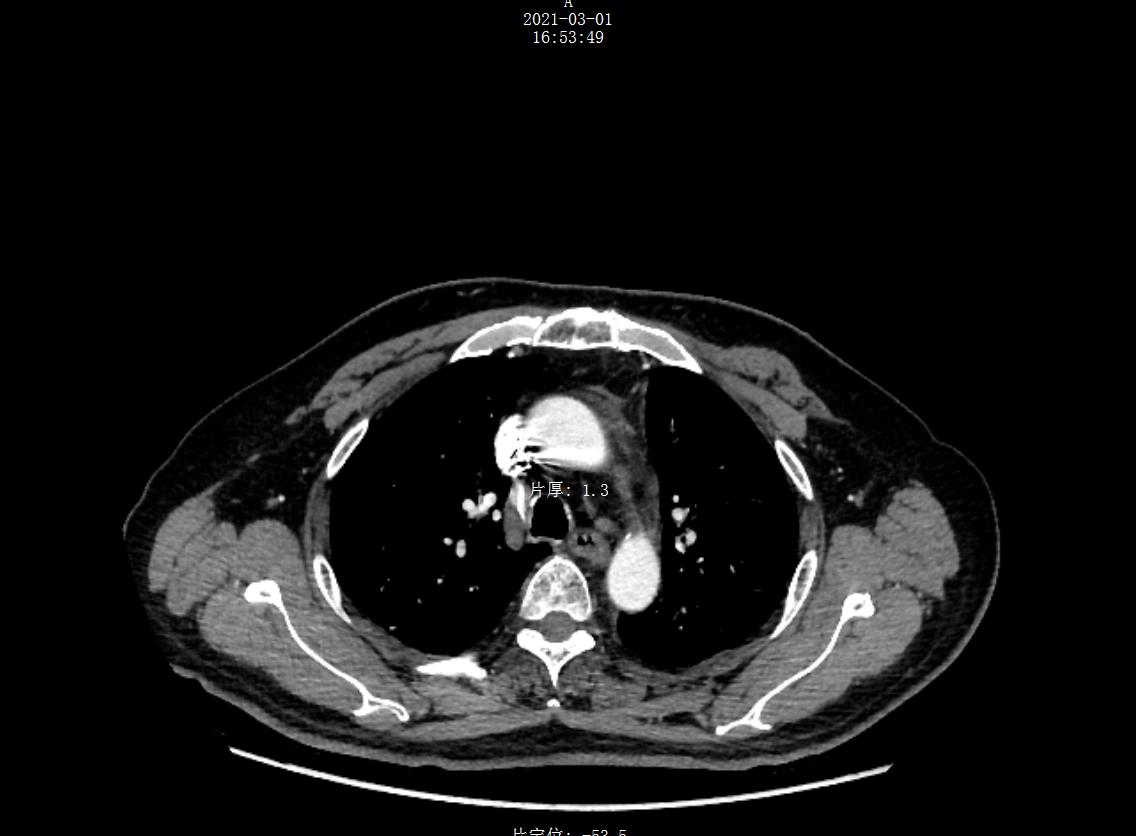

射波刀(CyberKnife)是当代社会最先进的全身立体定向放射治疗设备,具有精准度高、无伤口、无痛苦、无流血、无麻醉、恢复期短、预后好、患者治疗后即...